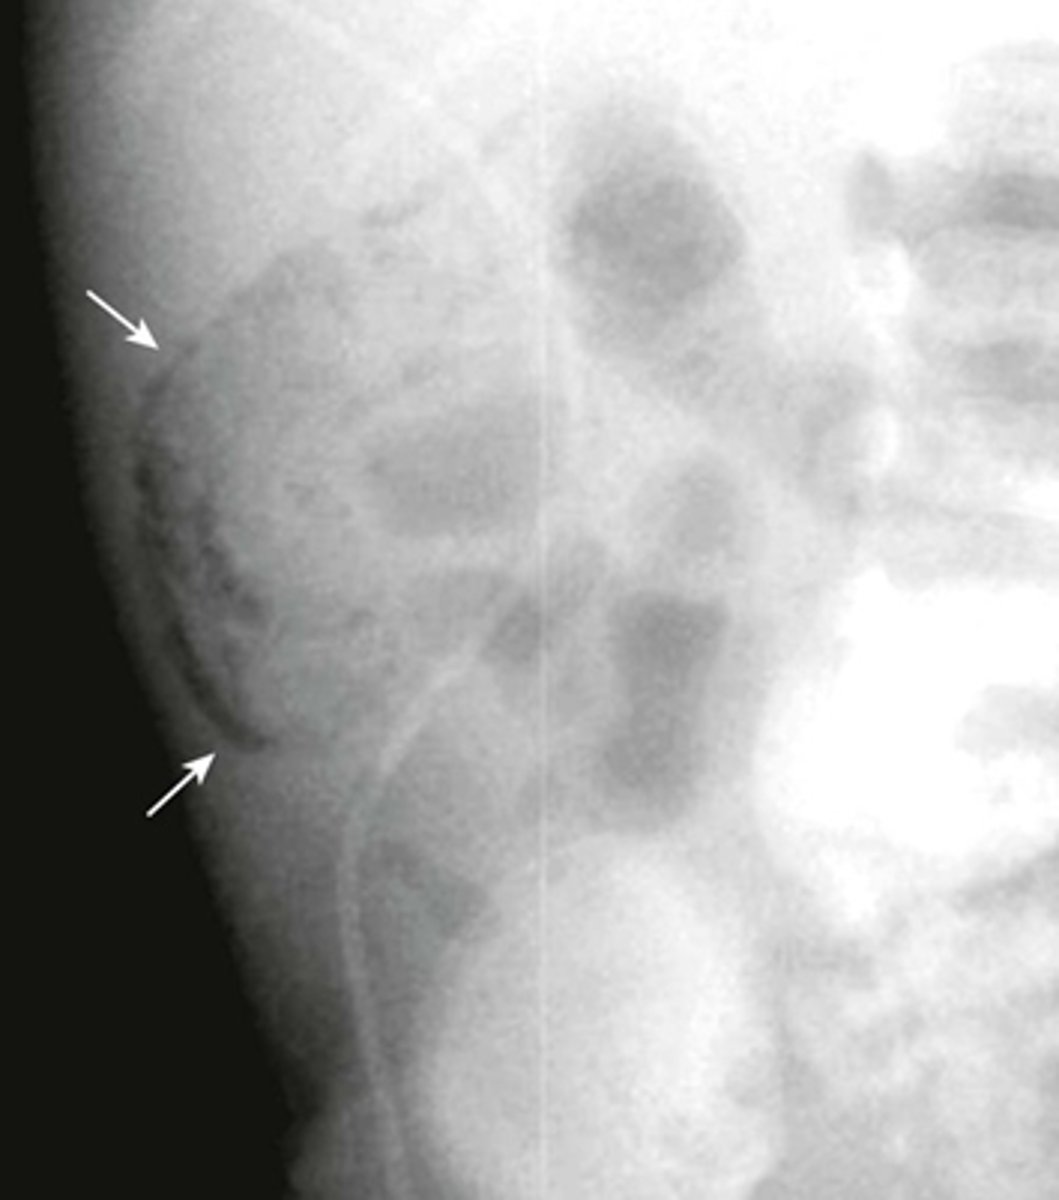

Pneumatosis - air in the abdominal wall.

WHITE ARROWS - RLQ demonstrating thin curvilinear lucency that parallels with the lumen of the adjacent bowel.

Appearance characteristic of gas in the bowel wall.

In infants the MC cause for this finding is necrotizing enterocolitis - a disease found mostly in premature infants in which the terminal ileum is most affected.

Pneumatosis intestinalis is pathognomonic for necrotizing enterocolitis in infants.